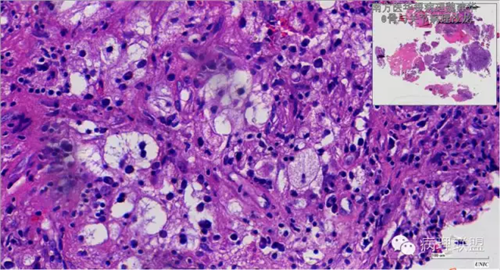

来源于组织细胞的相似性骨病ECD vs RDD 看图说话

病例由南方医华银病理魏建华提供,致谢。